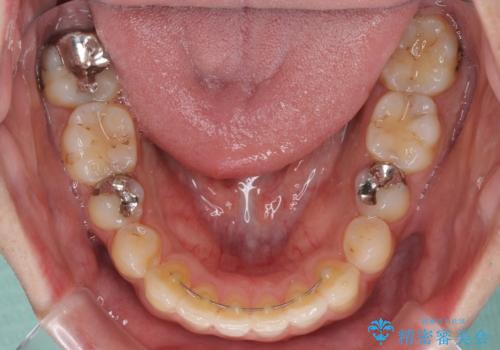

再矯正後の後戻りを防ぐため、歯列排列後に、下顎前歯はワイヤーによる固定を行いました。

下顎前歯の歯列を動かないようにしておくことで、上顎前歯の後戻り防止にも効果を発揮します。